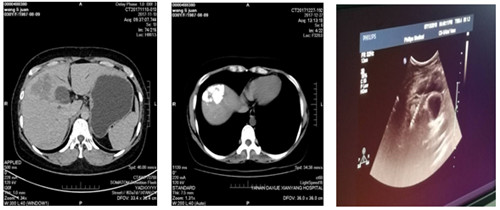

2018年5月前我院腫瘤胸外科收入一年輕女性患者,檢查確診為肝癌,經(jīng)腫瘤多學(xué)科會(huì)診后,行多次肝動(dòng)脈灌注化療栓塞術(shù),治療過(guò)程順利,現(xiàn)復(fù)查CT示碘油沉積區(qū)域面積較前減小。為使病人得到最佳治療,在我院腫瘤病院張海濤院長(zhǎng)主持下,召開(kāi)了腫瘤多學(xué)科會(huì)診MDT,經(jīng)過(guò)充分的討論,制定了嚴(yán)謹(jǐn)?shù)闹委煼桨?,確立現(xiàn)在的最佳治療方法為無(wú)痛肝癌射頻消融術(shù)。

在腫瘤胸外科苗滿園主任帶領(lǐng)下,由腫瘤外科、超聲科及手術(shù)麻醉科組成的肝腫瘤微創(chuàng)治療團(tuán)隊(duì),在鎮(zhèn)痛麻醉后超聲引導(dǎo)下將電極準(zhǔn)確插入肝腫瘤內(nèi)部,采用雙針電極對(duì)肝腫瘤進(jìn)行射頻消融手術(shù)。整個(gè)手術(shù)過(guò)程約40分鐘,達(dá)到了預(yù)期滿意效果及消融范圍。術(shù)后患者有輕微不適,無(wú)出血及鄰近臟器損傷。